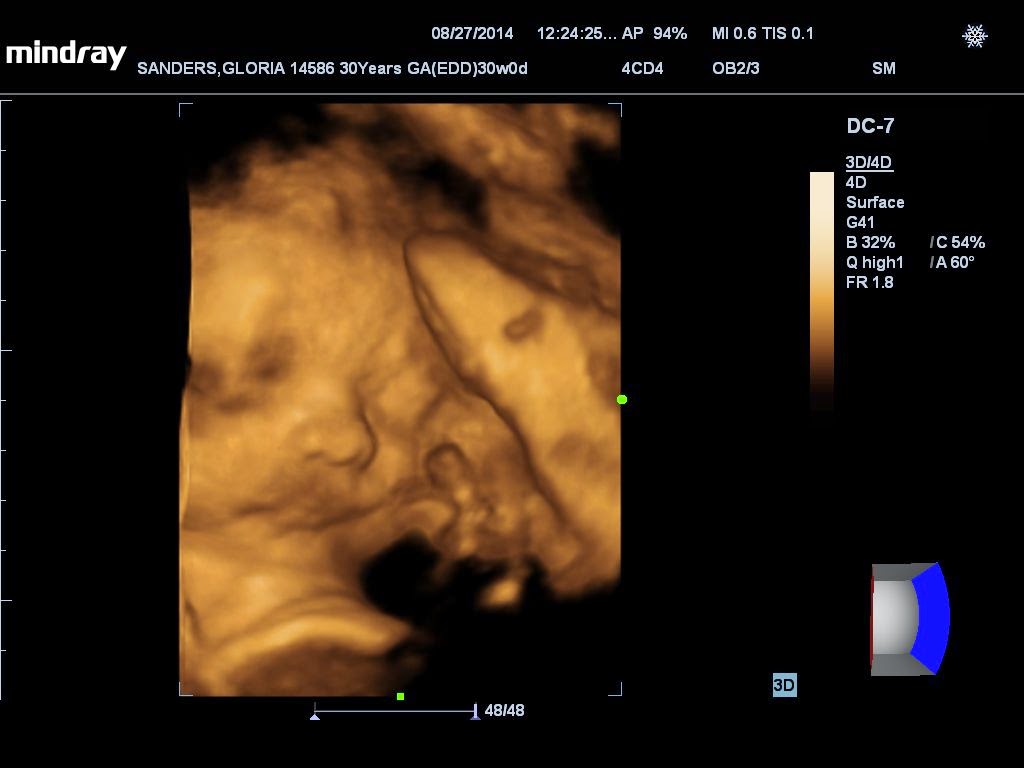

FIRST ROUND OF PICS - LEVI'S 4D ULTRASOUND (30 Weeks).

So glad he cooperated. We got some great pics of this cute little dude.